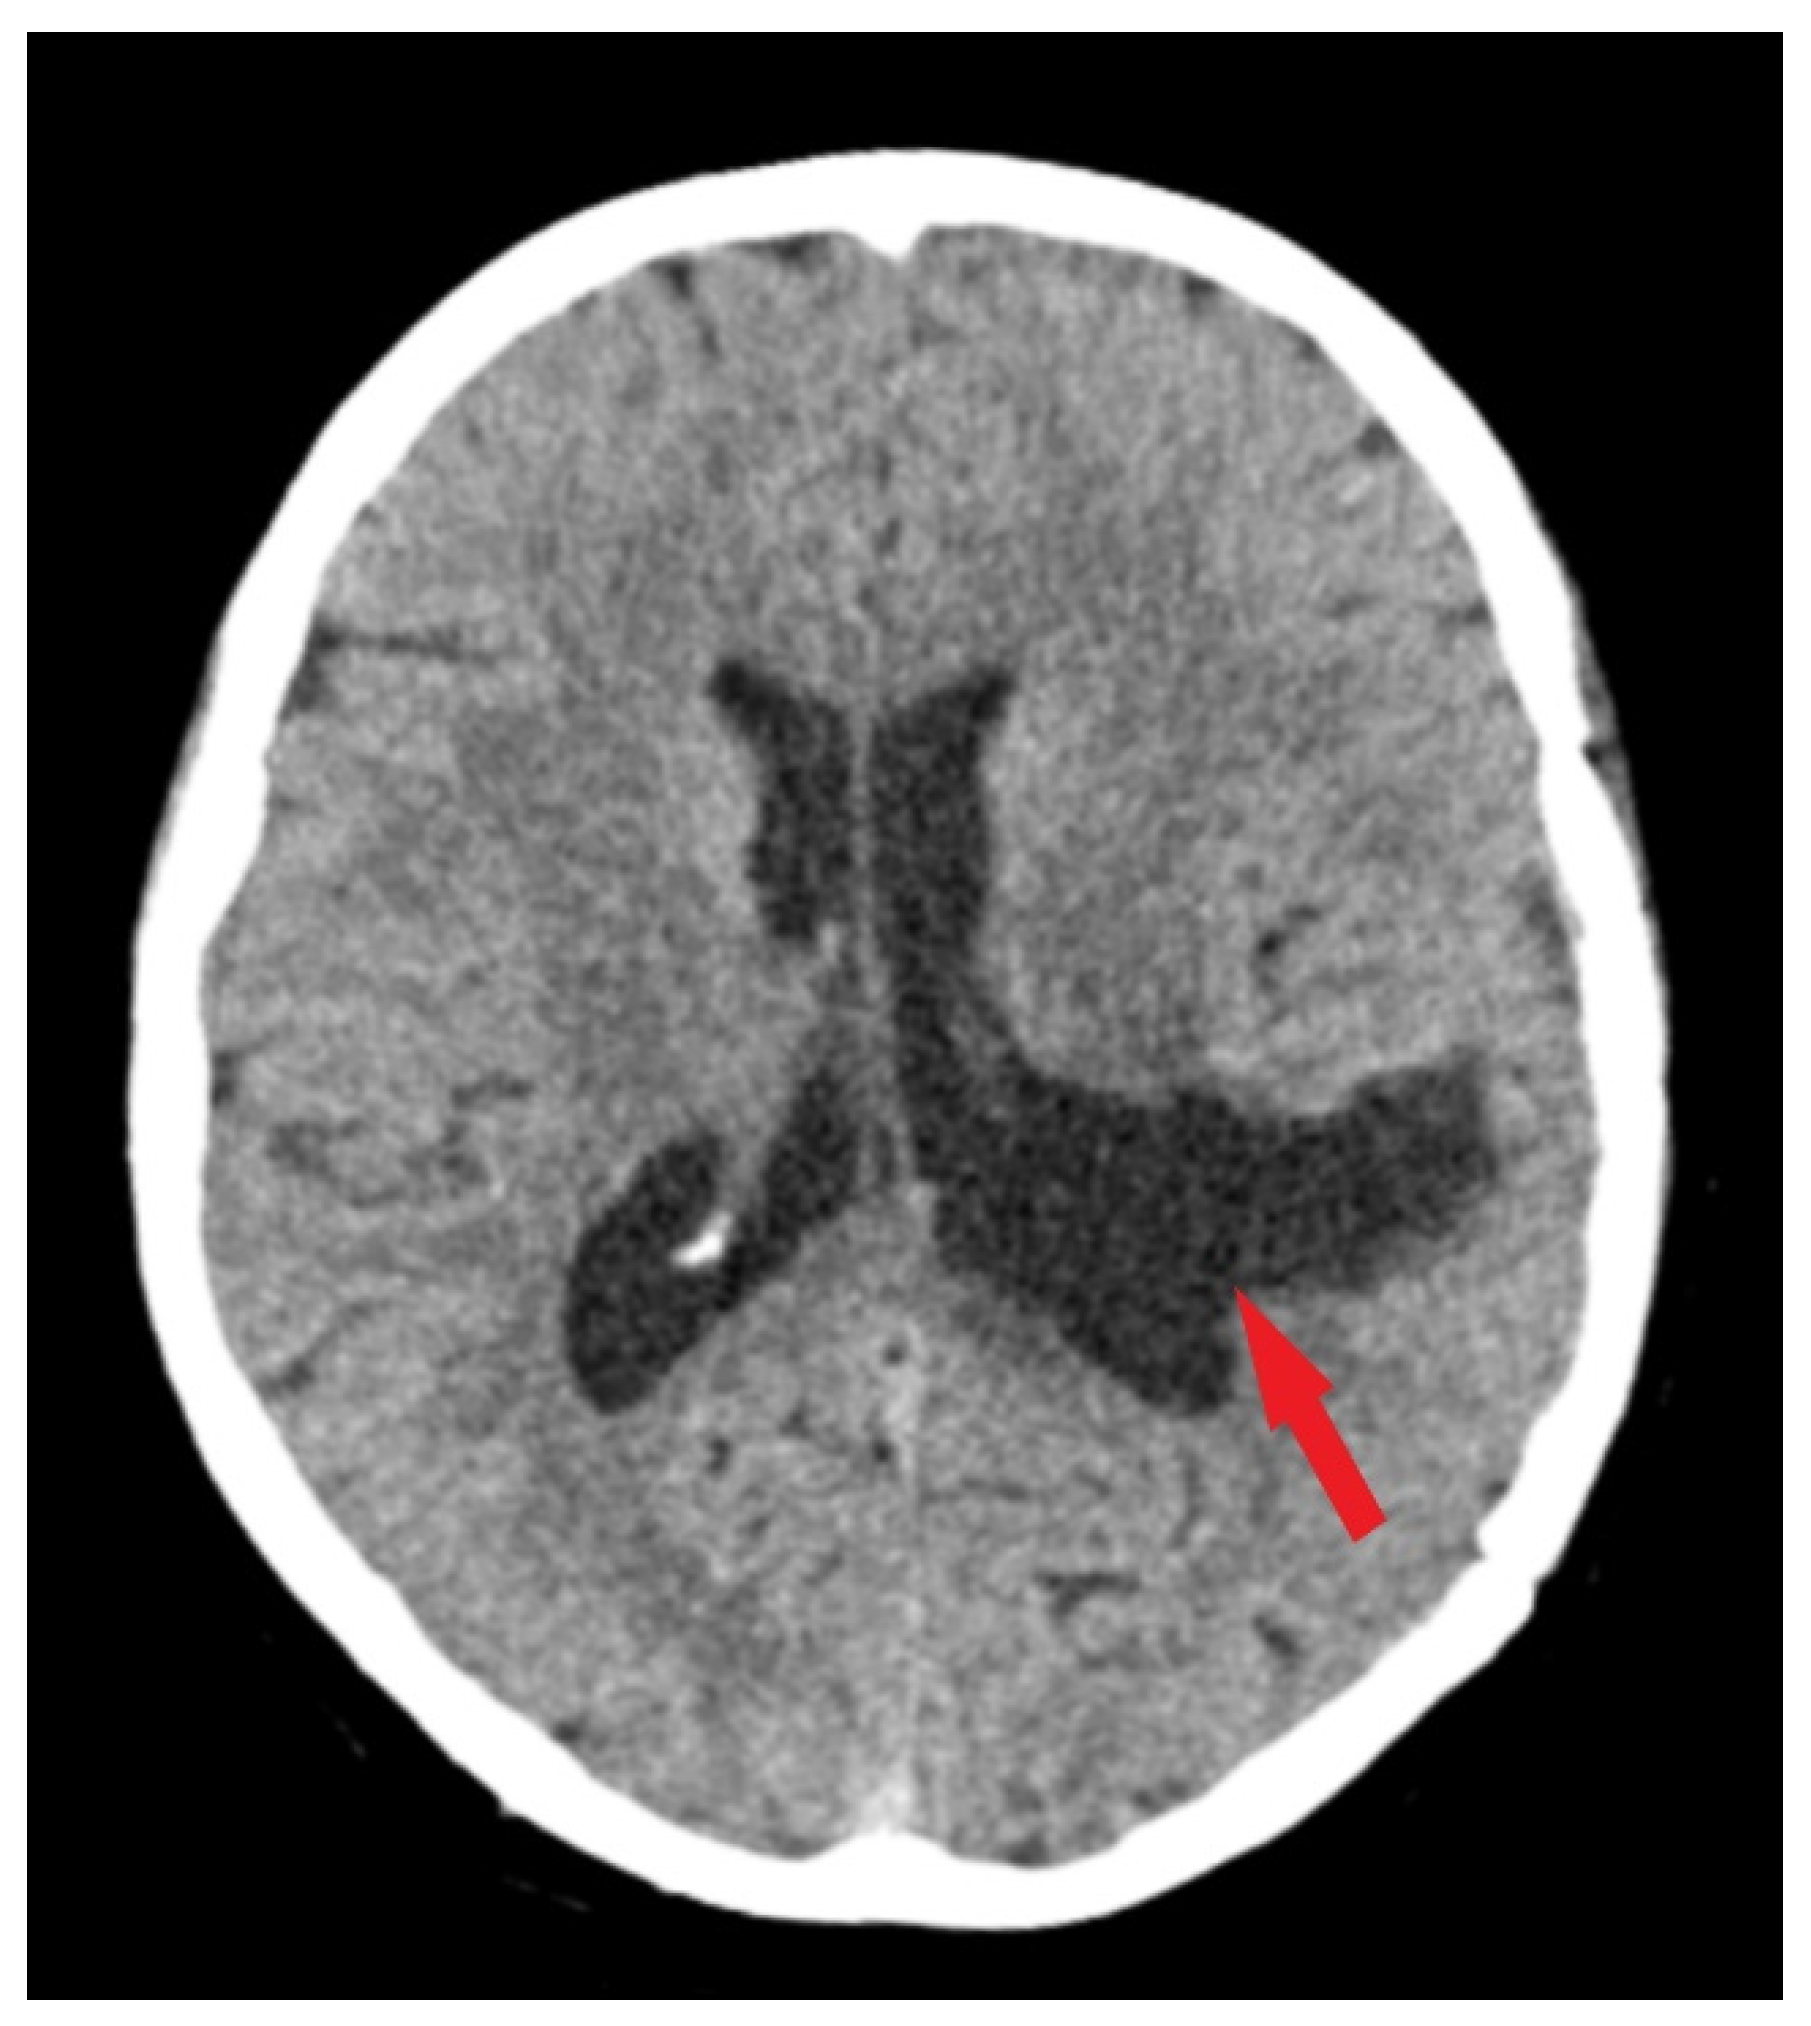

Under general anesthesia, a surgical procedure involving a left temporoparietal craniotomy was executed. This was followed by the excision of an intraventricular meningioma situated in the body of the left lateral ventricle under microscopic guidance. We have used this approach in order to exclude the risk of a seizure disorder. Complete resection of the tumor was accomplished (Figure 3), and subsequent histopathological analysis confirmed the tumor as a fibrous meningioma (Figure 4).

Figure 3.

Postoperative CT scan. Tissue window of CT scan highlights total removal of the intraventricular meningioma (red arrow) with edema remission.

Follow-up evaluations at 3 months and 1 year post-surgery revealed mild, predominantly expressive mixed aphasia. Non-contrast CT scans identified a region of hypodensity in the left temporo-parietal area, indicative of post-surgical changes without any mass effect or contrast uptake, suggesting a sequela. No evidence of tumor recurrence or residual meningioma was observed (Figure 5). Throughout the follow-up period, the patient was maintained on antiepileptic medication, with no reported episodes of seizures.